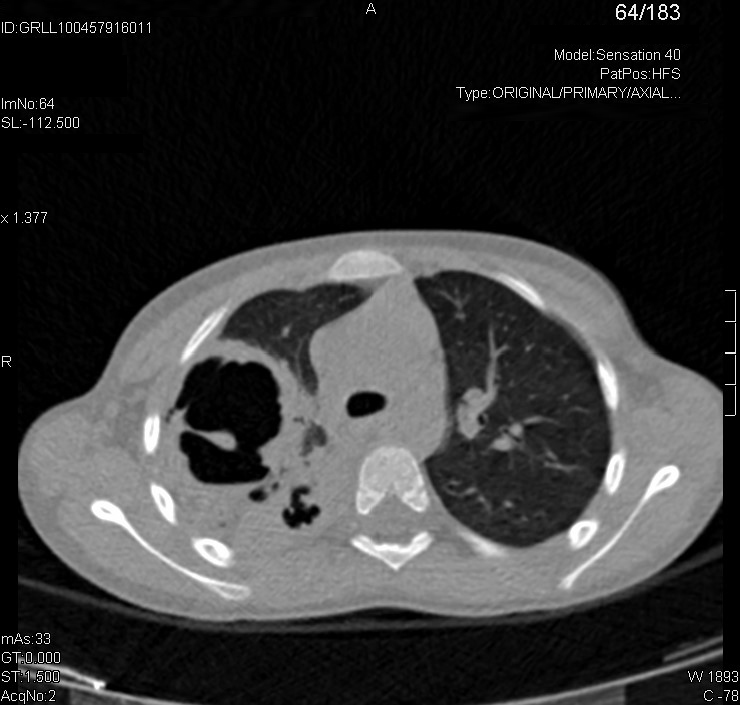

Para determinar si las imágenes de la radiografía son únicas o múltiples y definir con mayor precisión las características de las lesiones, pedimos una tomografía computarizada (TC).

La TC se informa de la siguiente manera: “En el hemitórax derecho se aprecian tres cavidades, una localizada en el lóbulo superior derecho y dos en los segmentos superiores del lóbulo inferior derecho, de paredes gruesas que no parecen estar colonizadas, sugestivas de neumonías necrotizantes. En el parénquima pulmonar izquierdo no se aprecian alteraciones significativas”.